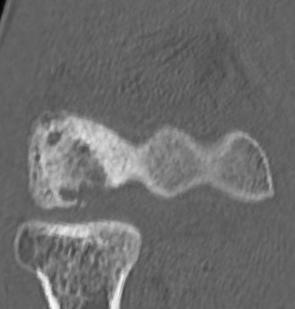

CT画像①

上腕骨小頭に骨欠損

②

上腕骨小頭に遊離体

③

同じく遊離体